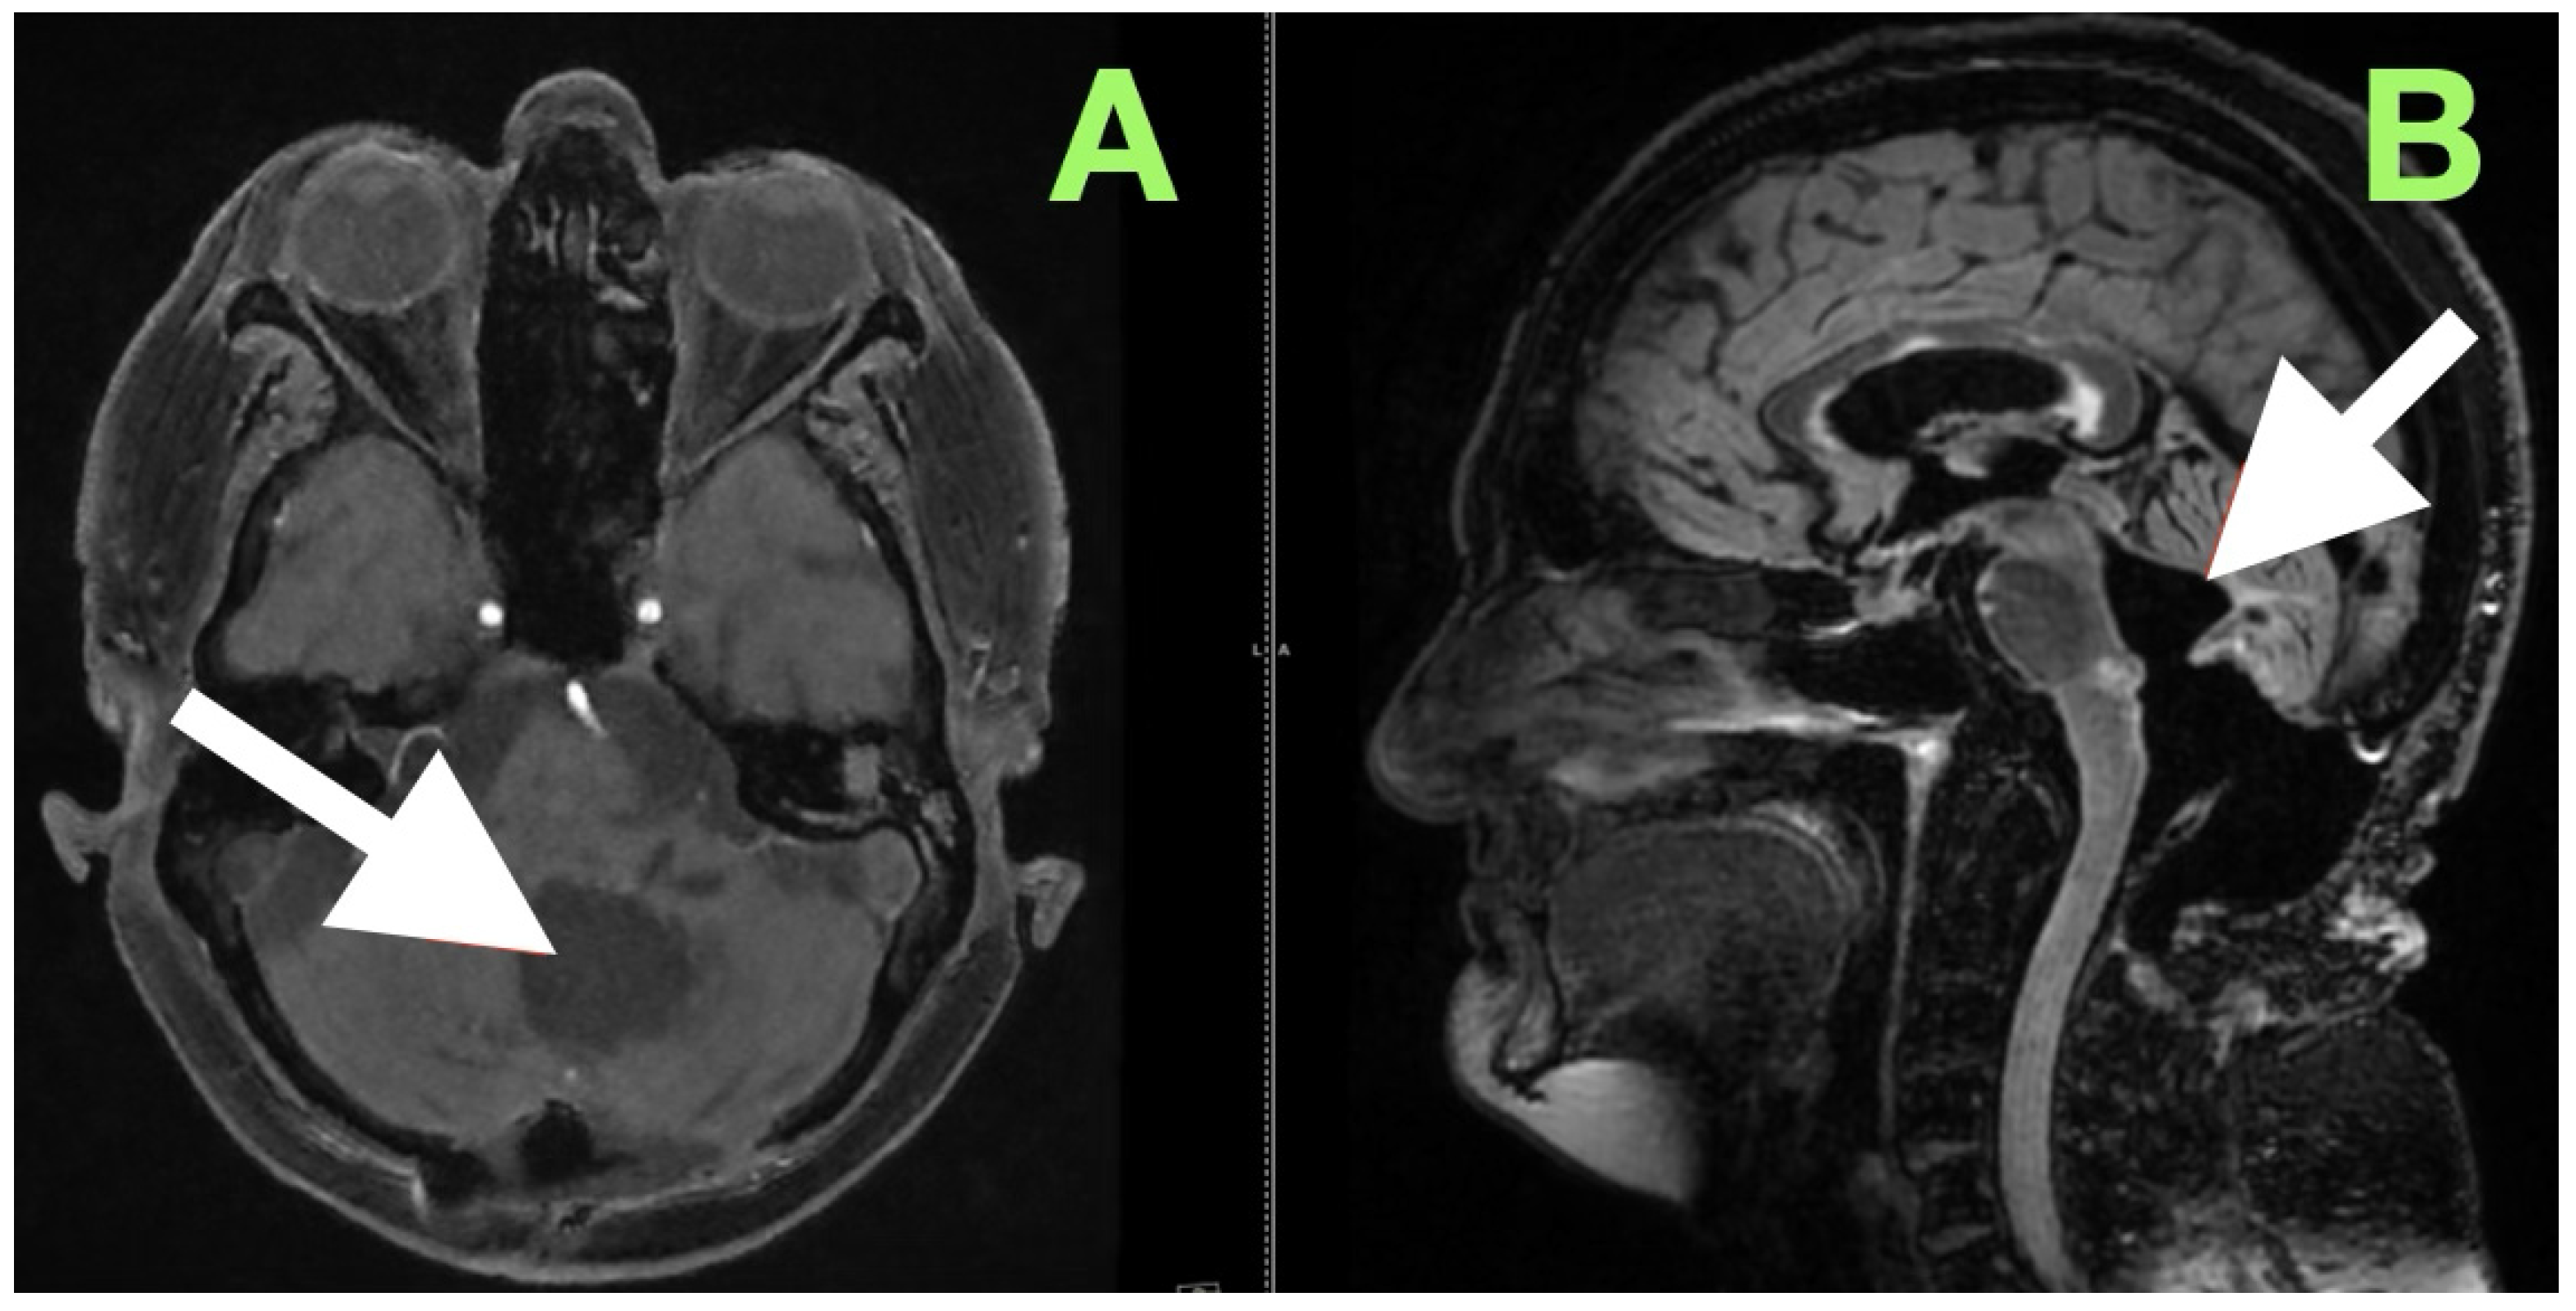

High-resolution MRI with selective MRA was obtained immediately after the examination to determine the spatial extent of the mass, vascular relationships to it, and to evaluate the current status of cerebrospinal fluid dynamics. Sagittal MRA reconstruction (Figure 1) revealed a large extra-axial mass in the left posterior fossa that centered on the cerebellar hemisphere and extended medially into the vermis. Posterior fossa arteries were lengthened and changed their course: the posterior inferior cerebellar artery (PICA) appeared to follow an elongated superior–posterior course along the dorsal surface of the mass with maintained continuity and caliber, the anterior inferior cerebellar artery (AICA), and small cerebellar perforators were also pushed to the left but appeared to be unaffected. The gradual vascular displacement without distortion, alteration, or irregularity would be consistent with chronic adaptive remodeling of the vessels; acute distortion did not occur, and there was no vascular blush, arteriovenous shunt, and/or feeding-vessel hypertrophy, identifying the extra-axial mass as an avascular, space-occupying lesion consistent with an epidermoid tumor.

Figure 1. Preoperative magnetic resonance angiography, sagittal reconstruction, demonstrating a large extra-axial mass in the left posterior fossa centered in the cerebellar hemisphere with medial extension toward the vermis. The lesion produces smooth elongation and displacement of adjacent posterior fossa arteries, most prominently the posterior inferior cerebellar artery (PICA, white arrow), which is draped over the superior–posterior surface of the mass. Vessel continuity and caliber are preserved, indicating chronic adaptive displacement rather than acute encasement or invasion. The absence of abnormal vascular blush or arteriovenous shunting supports the impression of an avascular lesion, consistent with the imaging profile of an epidermoid tumor.